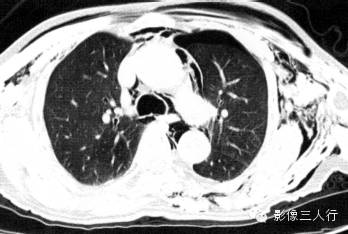

报告书写:胸廓对称,双侧肺野透光度降低,双侧肺门不大,双侧皮下、纵隔内可见线状透亮的气体阴影,气管外壁清楚(图1)。

图1纵隔气肿